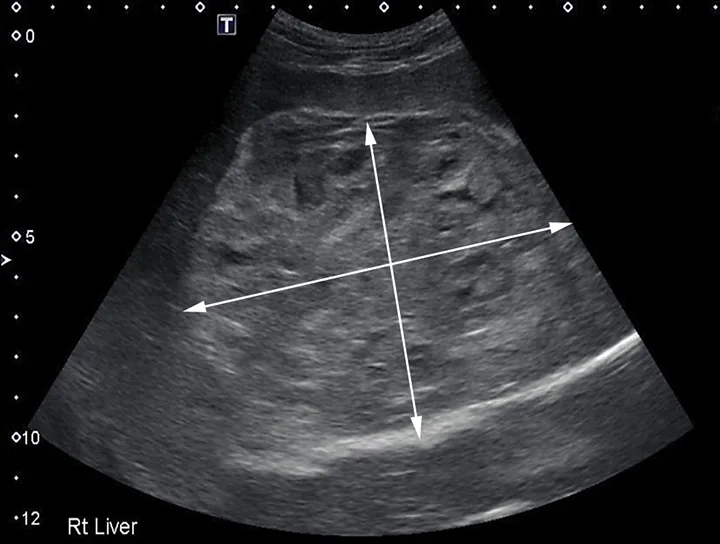

Ultrasonographic appearance of a cavitary mass measuring >10 cm in the left liver on initial presentation. Area of mass demonstrated by arrows

Mild leukocytosis (17.3 × 103/μL [17.3 × 109/L]; reference range, 4.3-13.6 × 103/μL [4.3-13.6 × 109/L]) and mild regenerative anemia (hematocrit, 33% [reference range, 40%-57%]; reticulocytes, 150 000/μL [150 × 109/L]) were noted. The remainder of the CBC, coagulation profile, and serum chemistry profile were within normal limits. Abdominal ultrasonography demonstrated a large (>10 cm in diameter) hepatic mass (Figure 1) originating from the left aspect of the liver that contained numerous variably sized anechoic regions and mild anechoic peritoneal effusion. Two smaller masses were visible in the hepatic parenchyma (Figure 2). Ultrasound-guided fine-needle aspiration of the large hepatic mass was performed, and cytology showed evidence of previous hemorrhage and mild extramedullary hematopoiesis. Ultrasound-guided biopsies were not considered safe because of the risk for hemorrhage due to the cavitated nature of the masses. The top differential diagnosis was malignant neoplasia (eg, hemangiosarcoma, histiocytic sarcoma, hepatic adenocarcinoma); benign (eg, hemangioma) or infectious (eg, fungal or parasitic) lesions were considered possible but unlikely. Thoracic radiographs were unremarkable.